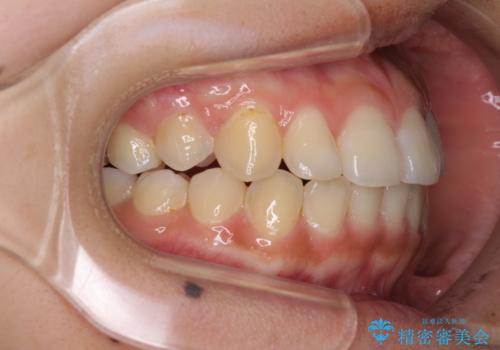

前歯の突出感とデコボコ インビザラインで改善

- 上下前歯のデコボコを気にして来院された患者様です。

インビザラインによる上下歯列の側方拡大と後方移動、IPR(歯と歯の間を削る)にるスペースの獲得により歯列を整えることとしました。

右上の小臼歯は歯根癒着をしており、様々な方法を試みるも動かすことができませんでした。

それでも奥歯のかみ合わせに不自由はなく、歯列をきれいに整えることができました。